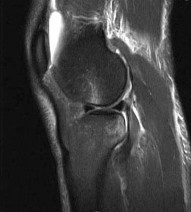

Question 1:

A 45-year-old recreational athlete presents with acute medial knee pain after feeling a 'pop' while deep squatting. MRI demonstrates an extrusion of the medial meniscus of 4 mm and a complete radial tear at the posterior root. Which of the following best describes the primary biomechanical consequence of this specific injury pattern?

Options:

- Increased anterior tibial translation at 30 degrees of knee flexion

- Loss of hoop stresses leading to peak contact pressures equivalent to a total meniscectomy

- Increased varus laxity in full extension

- Decreased contact area restricted primarily to the patellofemoral joint

- Increased shear forces leading directly to a rupture of the anterior cruciate ligament

Correct Answer: Loss of hoop stresses leading to peak contact pressures equivalent to a total meniscectomy

Explanation:

A posterior medial meniscus root tear disrupts the circumferential hoop stresses that the intact meniscus relies on to dissipate axial loads. Biomechanical studies demonstrate that a posterior root tear is functionally equivalent to a total meniscectomy in terms of decreasing contact area and dramatically increasing peak tibiofemoral contact pressures, leading to rapid chondrolysis and osteoarthritis if left untreated.